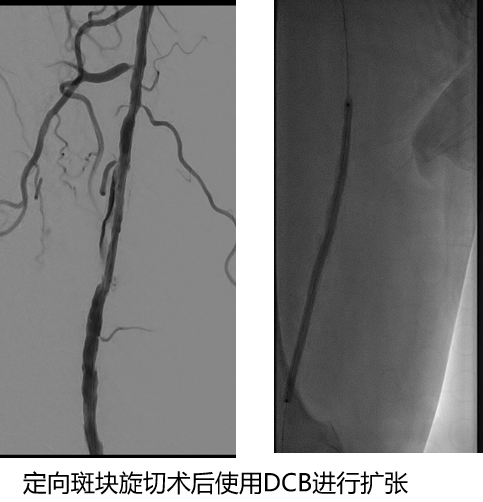

严重的钙化斑块——定向斑块旋切术

针对严重钙化斑块,可预扩后使用Hawk进行减容

★ 定向斑块旋切术

无限流性夹层的发生

避免支架植入

腘动脉、胫腓干的短段闭塞

★ 巧克力球囊

股浅动脉、

腘动脉与胫腓干病变

ELUVIA™ 6-120mm,6-80mm用于股浅

Chocolate 4-150mm, Sterling™ 4-20mm,

DCB 4-150mm